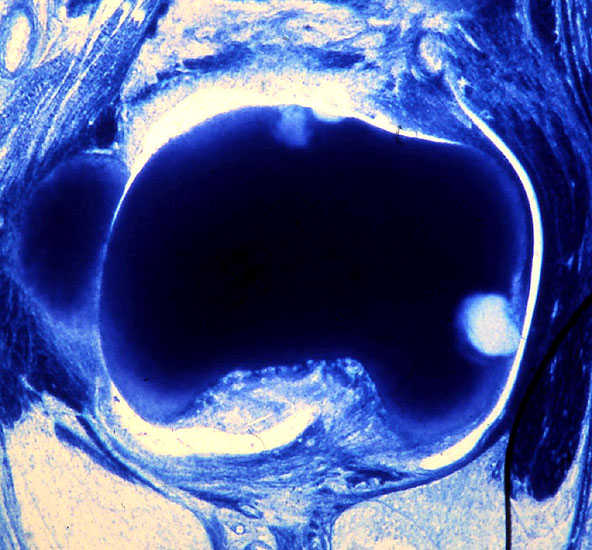

• Hallux valgus interphalangeus (Abb.1, Abb.2)

• Röntgenaufnahme des Fußes (unter Belastung) in dorsoplantarem und seitlichen Strahlengang (Abb. 2a-b).

• Beurteilung des proximalen Gelenkflächenwinkels der Grundphalanx (Proximal Phalangeal Articular Angle, PPAA) sowie des distalen Gelenkflächenwinkels der Grundphalanx (Distal Phalangeal Articular Angle, DPAA) 56 (Abb. 3c und 3d).

• Bestimmung des ersten Intermetatarsalwinkels (IMA, Abb. 3a), des Hallux valgus Winkels (HVA, Abb. 3a), des distalen metatarsalen Gelenskflächenwinkels (Distal Metatarsal Articular Angle, DMAA, Abb. 3b) 7. Möglicherweise muss die Akin-Osteotomie mit weiteren Eingriffen kombiniert werden (z.B.: retrokapitale Osteotomie oder andere metatarsale Osteotomie; Arthrodese).